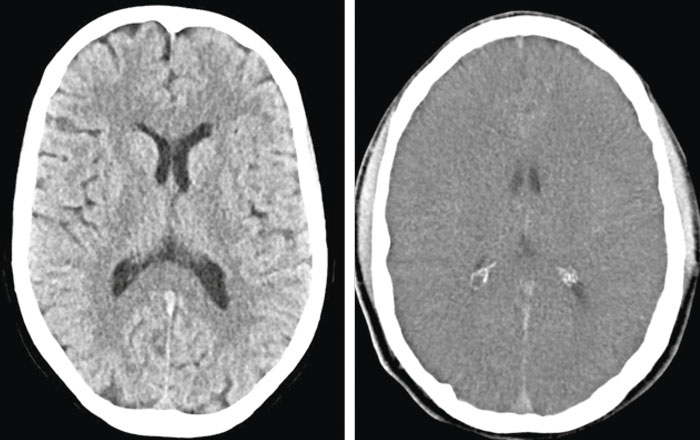

Mindre uttalade ischemiska/anoxiska förändringar är ofta svåra att påvisa och bedöma med hjälp av DT, och för neurologisk prognosbedömning rekommenderas främst undersökning med magnetresonans (MR) 3–5 dagar efter hjärtstoppet, eftersom MR-bil­den utvecklas över tid. Diffusionsviktade bilder med beräknad »apparent diffusion coefficient« (ADC), som avspeglar medeldiffusionen i varje bildelement, är överlägsna konventionella MR-sekvenser för att påvisa akuta hypoxiska/ischemiska lesioner.

Den nedsatta diffusionen i sådana områden ger hög signalintensitet (vitt) på diffusionsviktade bilder och låg signalintensitet (svart) på kvantitativ ADC-karta (Figur 4). Bilaterala utbredda eller multipla lesioner med nedsatt diffusion i kortex, djup grå substans och lillhjärna är förknippade med dålig prognos.

I en nyare studie med strukturerad visuell skattning av akuta diffusionslesioner nådde man 0 procent falskt positiv frekvens och 55–60 procents sensitivitet för dåligt utfall [35]. I studier med ADC-mätning har låga värden i olika regioner eller i hela hjärnan associerats till dålig prognos. Nyligen fann man vid retrospektiv semiautomatisk diffusionsanalys i en multi­centerkohort med 125 patienter att ADC <650 × 10-6 mm2/s i minst 10 procent av hjärnans volym gav 9 procent falskt positiv frekvens och 72 procents sensitivitet för dåligt utfall [36].

Icke desto mindre är tillgängliga MR-studier analystekniskt heterogena, och för såväl diffusionsviktade som ADC-baserade mätningar saknas säkra tröskelvärden för prognosbedömning i klinisk vardag.

Figur 4. Ischemiska/anoxiska skador i hjärna efter hjärtstopp visualiserade med magnetresonans. Överst till vänster: normal diffusionsviktad bild; överst till höger: omfattande kortikala skador som framstår vita på diffusionsviktade bilder; underst till vänster: normal bild med »apparent diffusion coefficient« (ADC); underst till höger: omfattande kortikala skador som framstår svarta på ADC-karta.